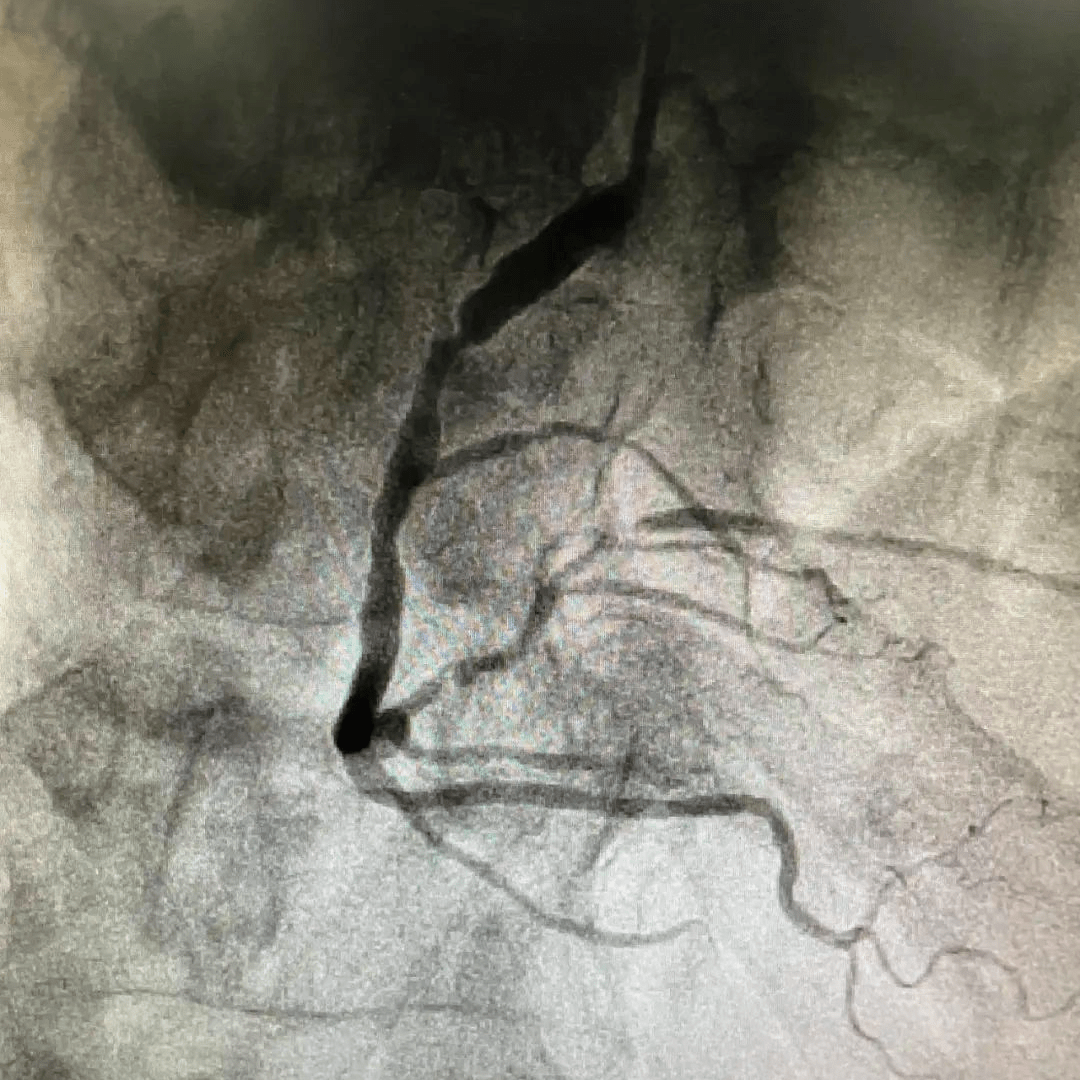

& optipass系统患者为72岁男性,因主诉"胸痛2年"入院,有高血压病史10

图片尺寸1080x1080